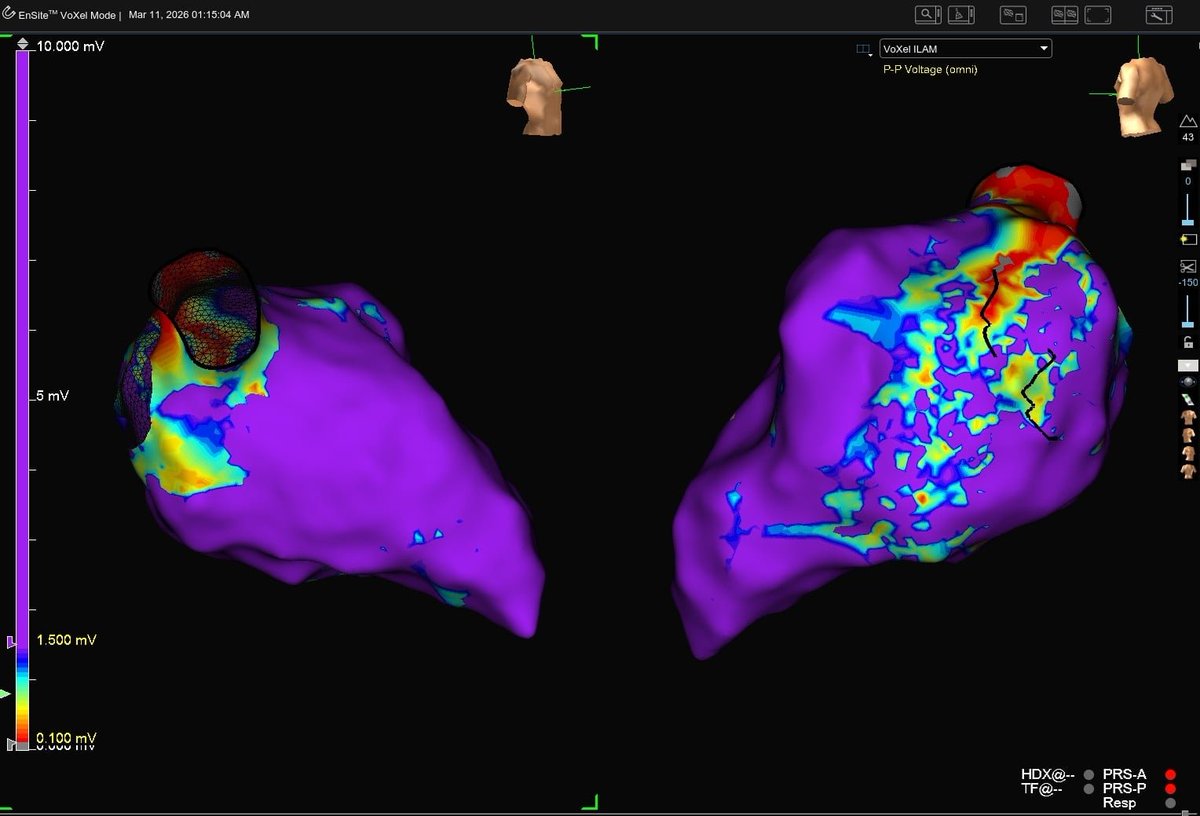

Patient presented with easily inducible tachycardia (CL ~510 ms). No discernible jump, but a long PPI suggested AVNRT. Made this beautiful map utilizing #HDGrid and #VoXel mode showing colliding wavefronts at the blue lesion. Several burns here = no more tachycardia #EnsiteX